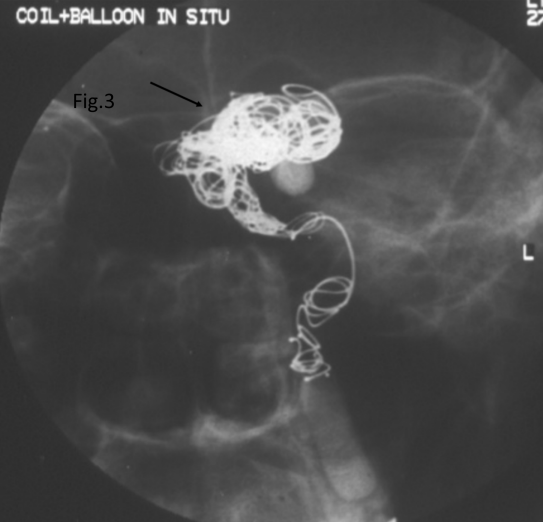

At second visit one month later, the anterior segment examination of both eyes showed similar findings. Dilated fundus evaluation of the left eye showed optic atrophy with attenuated arterioles and mild pigmented pale looking retina. Two weeks later, he underwent a successful angioembolization (Figure 3 [Fig. 3]). Subsequently, the patient was lost to follow-up.